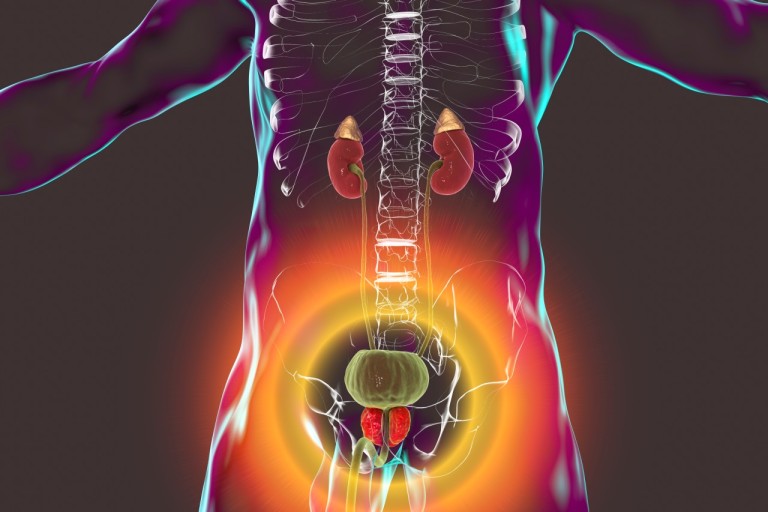

8. 골반통

골반 고통은 진행성 전립선암의 징후일 수 있어요. 고통은 일반적으로 옆구리, 배, 골반 부위에서 느껴지지만 암이 진행됨에 따라 뼈에서도 고통이 느껴질 수 있어요. 이런 부위에 고통이 있고 요로 감염 증상이 나타나면 의사를 내원해서 정확한 진단을 받는 것이 좋아요.